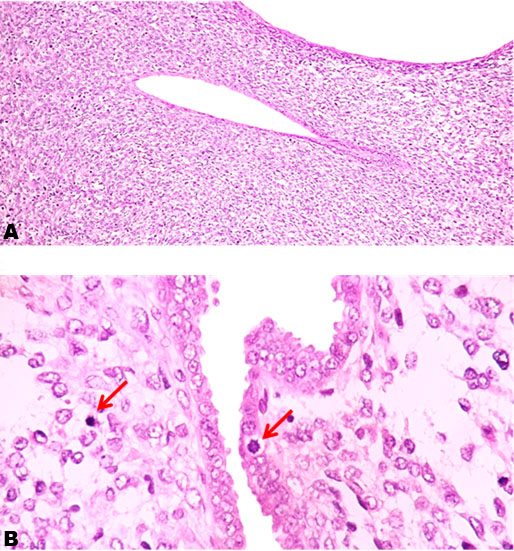

Histopathological analysis revealed a biphasic tumor composed of an expanded stroma with small round neoplastic cells with high nucleus:cytoplasmic ratio, oval nucleus with euchromatin, mild pleomorphism, and high mitotic activity (22 m in 10 HPF), this pattern represents more than 75% of the tumor. In other fields there were epithelial elements characterized by tubular glands covered by columnar neoplastic epithelium with oval nucleus with moderate pleomorphism and mitotic activity. The neoplastic cells invaded more than 2/3 of the myometrium and lymphovascular invasion was observed (Figure 2). The diagnosis of ASO was made with pathological stratification pT1b, pN0, pMx according of AJCC 8th ed and FIGO stage (2015): 1B. The rest of the samples were negative for neoplastic cells.

Figure 2: (A) Biphasic tumor with diffuse stromal overgrowth and tubular neoplastic glands. Histopathological analysis was performed on all the fragments stained with hematoxylin and eosin (H&E) 10×. (B) Mitotic activity in stromal and epithelial neoplastic cells.